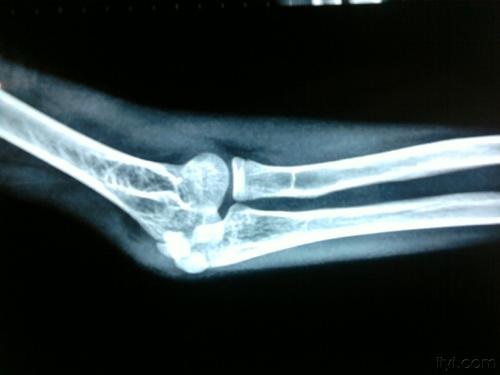

肘管综合征是指由于肘部受外伤或者其它原因引起发炎而导致尺神经受压,进而导致手部出现一系列的活动功能受限或障碍等症状。

张松健主任讲,肘关节骨折、肘外翻畸形、尺神经受牵拉或骨折复位不良,肘管内骨质不平,磨损到尺神经等会引发肘管综合征。抑或是肘管内发生囊肿等病变、骨性关节炎、类风湿性关节炎等,都可能导致肘管综合征的产生。